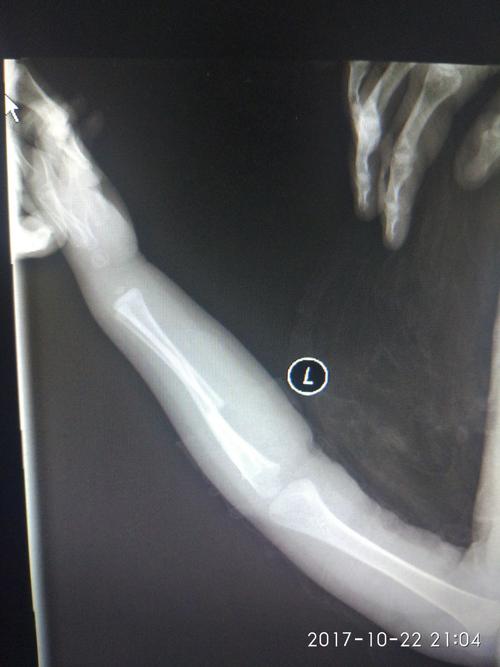

手臂左尺桡骨多段粉碎性骨折